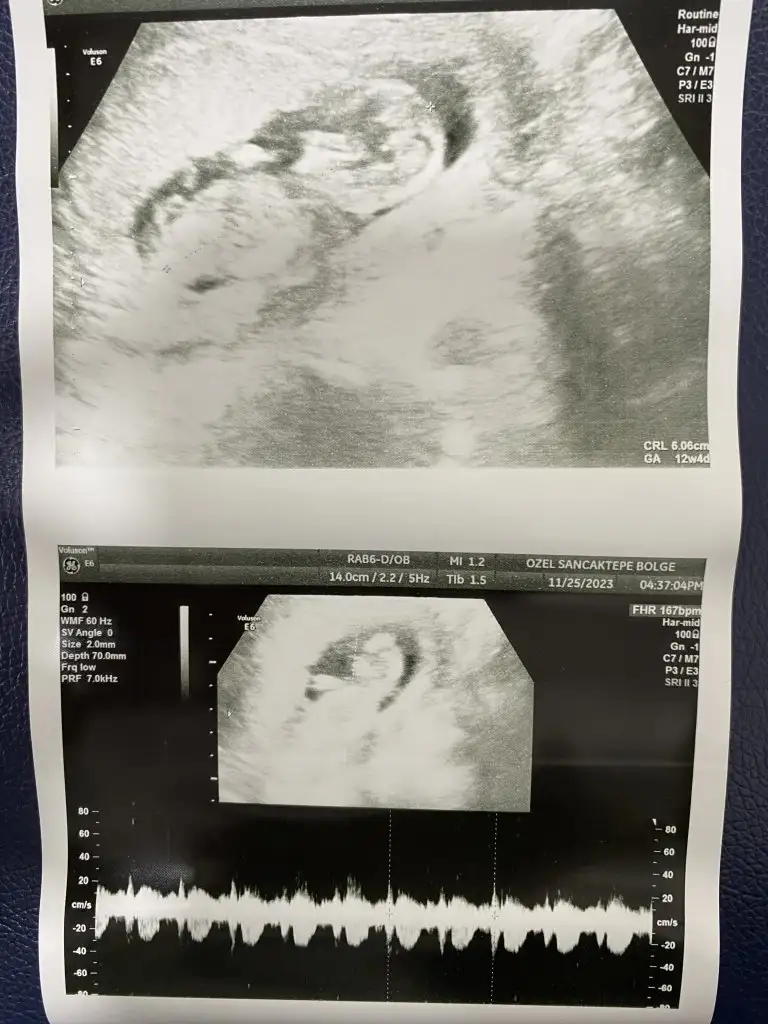

KizBanada tahmin yapar mısınız 13+3

Sizin çok erken ama bazı teorilere göre tahmin yapanlar varmış plesantanin sagindaysa erkek solindaysa kız gibi bilsem yapardimMerhaba bana da yorum yapar mısınız lütfennn vajinal bakıldı 6+3 te